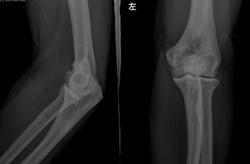

标题: X5007:女,40岁,时感局部隐痛。 [打印本页]

标题: X5007:女,40岁,时感局部隐痛。

关节间隙旁似见----游离体-----退变

骨内腱鞘囊肿

考虑:1.退变。2.痛风性关节炎,建议进一步检查。

退变,肱骨小头上方骨内腱鞘囊肿或滑囊疝

关节间隙变窄,并见增生,支持,退变

考虑肘关节退行性改变。